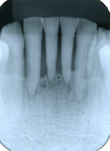

歯周病は歯の周囲組織を破壊していく病気です。その進行過程では歯の周囲骨の吸収も起こるため、レントゲン写真により骨の状態も検査します。

| 正常な歯 | 歯周病に罹患した歯 |